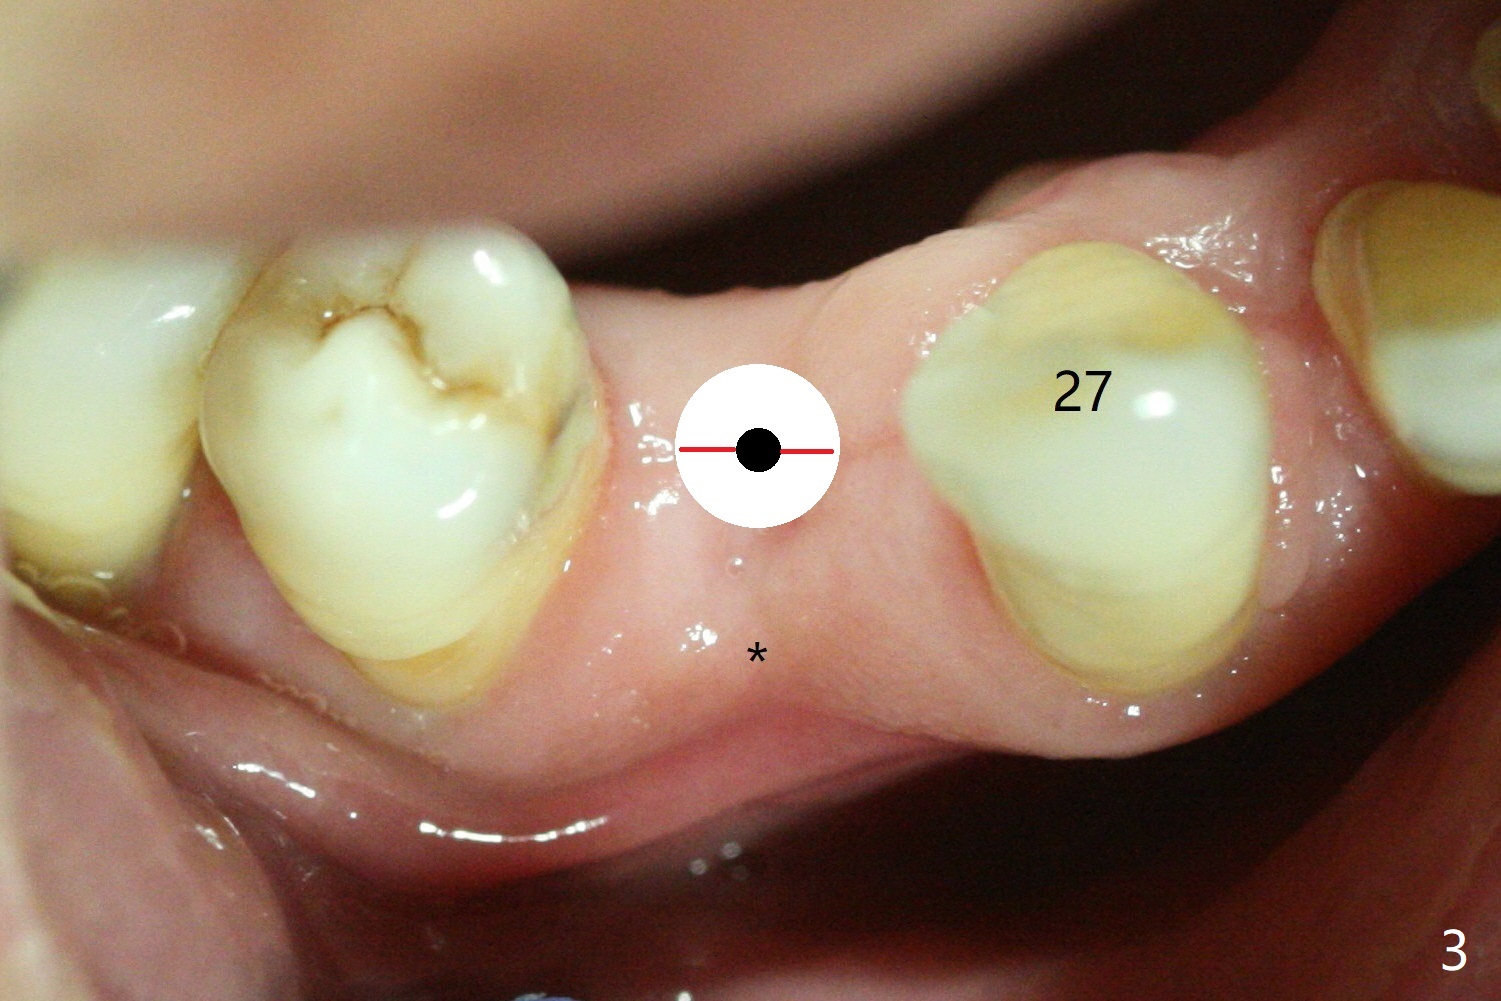

(*), followed by initial osteotomy using 2.2 mm drill with guide (Fig.2 small

dot). It may be necessary to remove the guide for ridge split using Magic Split or Tatum bone scalpel or blade

(Fig.3 red line). The buccal bone (Fig.4 red curved line) is